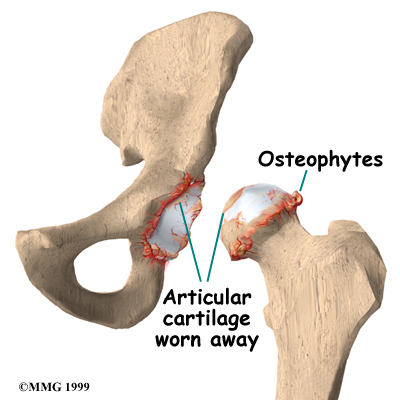

Articular cartilage is the smooth lining that covers the surfaces of the ball-and-socket joint of the hip. The cartilage gives the joint freedom of movement by decreasing friction. The layer of bone just below the articular cartilage is called subchondral bone. The main problem in OA is degeneration of the articular cartilage.

When the , or wears away, the subchondral bone is uncovered and rubs against bone. Small outgrowths called bone spurs or osteophytes may form in the joint.